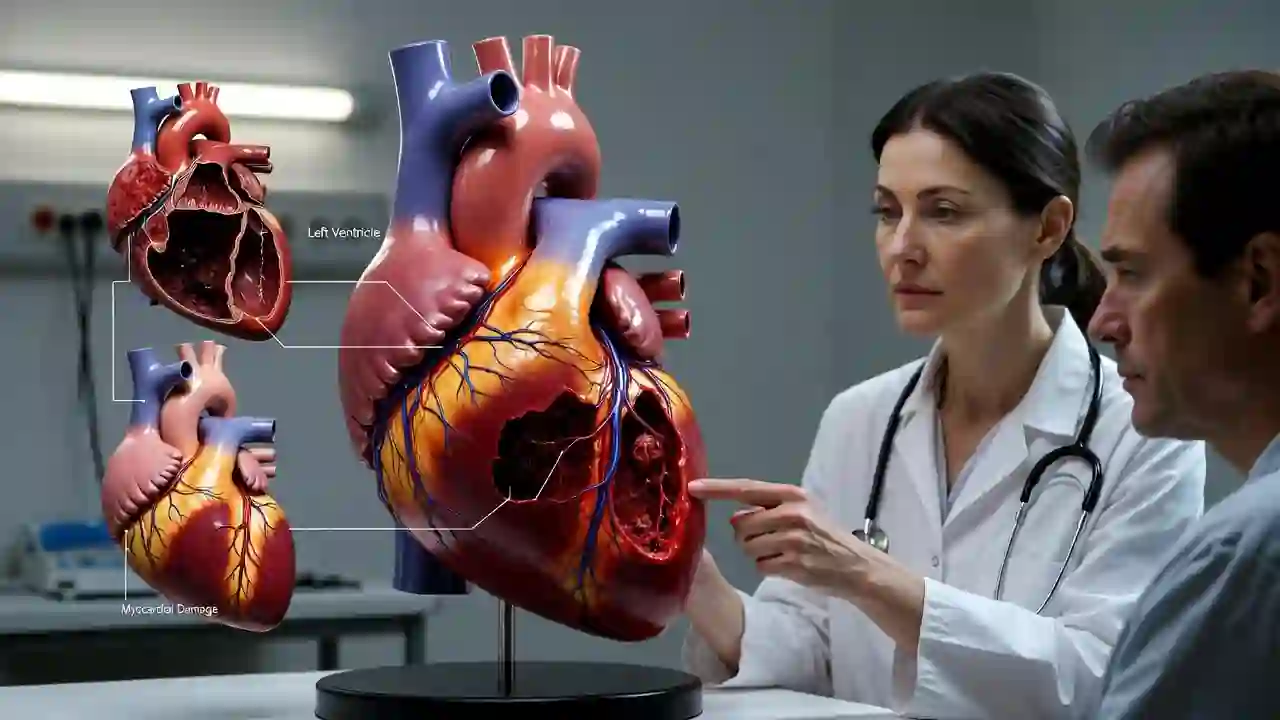

علل ضربان نامنظم بسیار متنوعاند. استرس، کمخوابی، مصرف کافئین، الکل یا برخی داروها میتوانند باعث آریتمیهای گذرا شوند. مشکلات ساختاری قلب، بیماریهای دریچهای، اختلالات تیروئید، فشار خون بالا یا بیماری عروق کرونر نیز از علل مهم آریتمیهای پایدار هستند.

در برخی موارد، پزشک از اکوکاردیوگرافی برای بررسی ساختار قلب و عملکرد دریچهها استفاده میکند. اگر احتمال بیماری عروق کرونر وجود داشته باشد، تست ورزش یا CT آنژیو ممکن است لازم باشد. انتخاب تست مناسب به علائم و شرایط بیمار بستگی دارد.